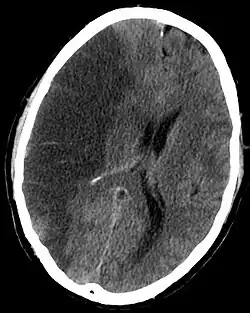

Aus der oben beschriebenen Problematik ergibt sich die Dringlichkeit der raschen ärztlichen Evaluation zur potenziellen Indikation einer Lysetherapie, deren wirksames Zeitfenster allgemein als 4,5 Stunden nach Symptomeintritt angesehen wird. Auch innerhalb dieses Zeitfensters für die Anwendung von Maßnahmen, welche geeignet sind die Blutversorgung wiederherzustellen, hat sich gezeigt, dass zur Minimierung bleibender Schäden ein frühestmöglicher Therapiebeginn angestrebt werden sollte. In der Darstellung fast aller Schlaganfall-Formen haben sich moderne MRT-Geräte mit spezialisierten, perfusions-diffusions-gewichteten und anderen spezialisierten Sequenzen (FLAIR, T2*) als überlegen erwiesen, aufgrund der häufig jedoch schlechteren Verfügbarkeit bei längerer Untersuchungsdauer ist die Notfalldiagnostik bei entsprender Anamnese und klinischem Bild nach wie vor häufig das CCT. Dieses eignet sich prinzipiell zum schnellen Ausschluss der primären Kontraindikationen der Lysetherapie mit RtPA, dem Vorliegen einer intracraniellen Blutung sowie eines Hirntumors. Besonders bei unklarem Symptombeginn ist das MRT jedoch in der Lage, durch Bestimmung eines Perfusions-Diffusions-Mismatchs, also die Darstellung eines Areals, über dem die perfusionsgewichtete Bildgebung schon auffällig, die diffusionsgewichtete jedoch noch nicht auffällig ist, einen Eindruck des schon geschädigten in Relation zum noch zu schädigenden Areal (Penumbra) zu geben.[10]